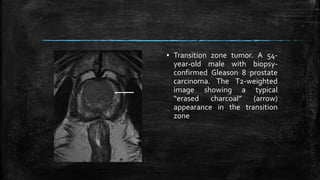

▪ Transition zone tumor. A 54-

year-old male with biopsy-

confirmed Gleason 8 prostate

carcinoma. The T2-weighted

image showing a typical

“erased charcoal” (arrow)

appearance in the transition

zone